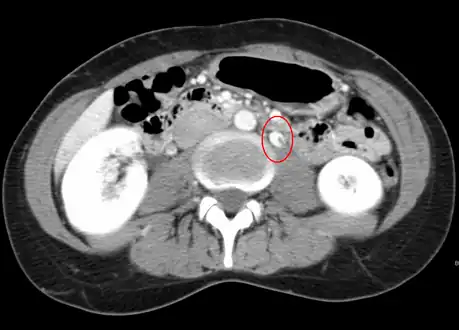

Left kidney with a suprarenal anechoic cyst-like lesion and hyperechoic intermedullary streaks in initial phase of renal vein thrombosis

CT showing dilatation and thrombosis of the left renal vein in a patient with nutcracker syndrome